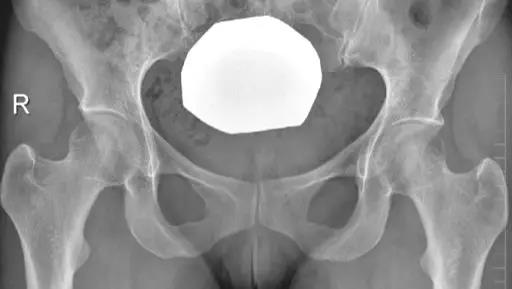

髋臼过深,髋臼窝线位于髂坐线内侧。

- 髋臼窝线位于髂坐线内侧。

- LCE>39°时,提示髋臼过渡覆盖。

- 正常髋臼指数(AI)为正值,AI为0或负值提示髋臼过深。

- 髋臼过深:髋臼线位于髂坐线内侧。

- 髋臼突出:更内侧(成人:男性>3mm,女性>6mm;儿童:男性>1mm,女性>3mm。)